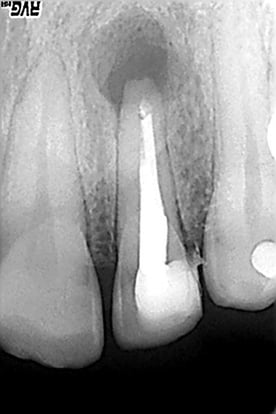

Iain’s rationale was that an apicectomy procedure encompasses all aspects of surgery including hard tissue, soft tissue and patient management. If you can put all of these 3 together with an eye for detail and a passion for doing things properly then you can achieve excellent results in all areas of your surgery.